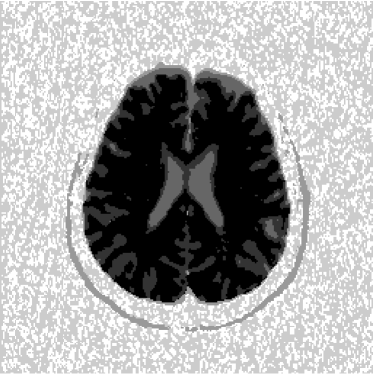

Figure 1: Axial DW-MR image of 13th slice with diffusion exponent of 0 s/mm2

To perform the training we chose 13th slice of each volume sample (figures 1, 2 and 3), once this slice shows the temporal corni of the lateral ventriculi. The exhibition of such structures facilitates the analysis of the specialist and helps him to find a correlation between data generated by our computational tool and a priori specialist knowledge. Furthermore, slice 13 presents a considerable amount of artifacts out of the cranial region.